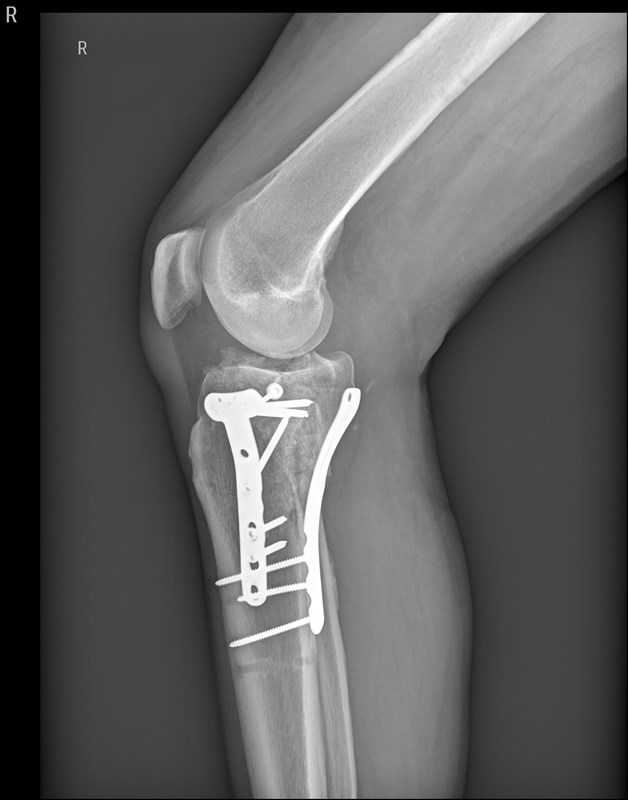

Lange Rede, kurzer Sinn, Schienbein rechts innen durch den Zylinder zerschmettert!

Erstes O.P. Externer fixateur,

Zweiter O.P.-Bissjen titanium.